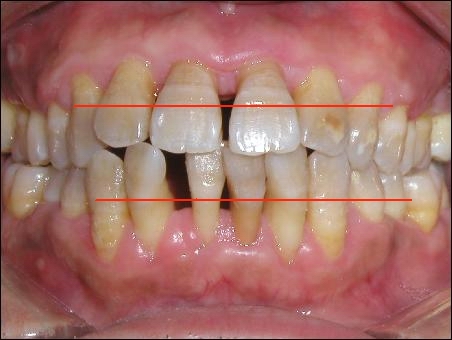

從外觀看,紅線標(biāo)注的位置,就是原來(lái)牙齦所在的位置

從上面這張圖,我們可以看出,牙周病是一個(gè)漸進(jìn)的過(guò)程,有可能長(zhǎng)達(dá)10年、20年。由于牙槽骨被吸收,牙齦逐漸萎縮。裸露在外面的牙齒就顯得越來(lái)越長(zhǎng)。有研究顯示,門(mén)牙的平均長(zhǎng)度一般在10—12毫米,年老后,這個(gè)數(shù)字可能會(huì)增長(zhǎng)到15—17毫米。過(guò)去認(rèn)為這是一種增齡性變化,但許多報(bào)告表明,老年人健康的牙齦并無(wú)明顯退縮。專家認(rèn)為成年人健康牙周組織的增齡變化,每10年退縮O.17毫米,由此推算老年人牙齦大約退縮O.7毫米,這在臨床上是不易觀察到的。而真正讓我們看到越長(zhǎng)越長(zhǎng)的牙齒,就是由牙周病引起的,而造成牙周病的罪魁禍?zhǔn)?,就是牙結(jié)石。那為什么我們天天刷牙,還會(huì)長(zhǎng)牙結(jié)石呢?